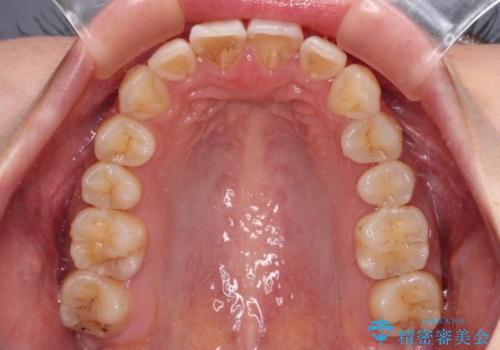

奥歯の咬み合わせはしっかりと改善され、前歯の突出感も改善されました。

- 前歯の突出感を気にして来院された患者様です。

左右ともに奥歯の咬み合わせが上顎前突となっており、上顎前歯が飛び出している状態でした。